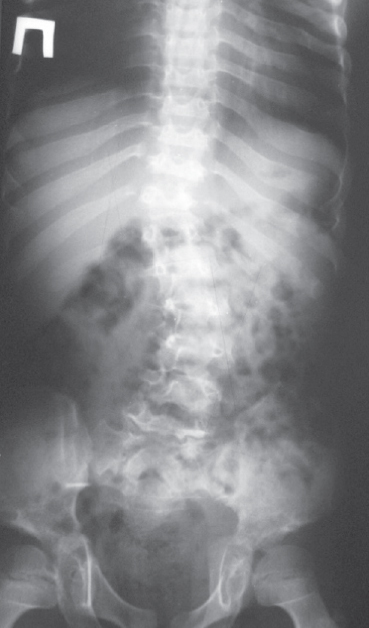

В 8 лет госпитализирован в СПбГПМУ для обследования. При осмотре отмечалась низкорослость: рост 105 см, вес 18,5 кг. Мальчик активный, подвижный. На осмотр реагирует адекватно, на вопросы отвечает правильно, ориентирован во времени и пространстве; обслуживает себя не полностью в связи с наличием контрактур суставов верхних конечностей. Знает стихи, рисует, помогает матери по дому. Признаки дизостоза: брахицефалия, деформация грудной клетки (килевидная грудная клетка с развернутой нижней апертурой), контрактуры суставов. Фенотип ребенка характерен для МПС: высокий лоб, готическое небо, короткая шея, низкорасположенные уши, макроглоссия, брахидактилия. Контрактуры и ограничение движений в плечевых суставах (не может поднять руки вертикально вверх), разгибательно-сгибательные контрактуры локтевых суставов (объем движений 45°), лучезапястных (объем движений 20°), сгибательно-разгибательная контрактура коленных суставов, резкое ограничение движений в голеностопных суставах. Деформация стоп. Х-образная деформация нижних конечностей (рис. 4). Кожные покровы чистые, смуглые (загар). Тоны сердца ритмичные, выслушивается систолический шум по правому краю грудины (шум недостаточности трикуспидального клапана), систолический шум (менее громкий) в точке Боткина и на верхушке сердца. Звучность тонов на верхушке сердца одинаковая (то есть I тон ослаблен), частота сердечных сокращений 86 в минуту. Дыхание везикулярное, проводится равномерно, хрипов нет. Живот симметричный, пупочная грыжа небольшого размера (диаметр пупочного кольца 1,5 см), гепатоспленомегалия (печень +6 см, селезенка +3 см из под края реберной дуги). При обследовании: на эхокардиографии гипертрофическая кардиомиопатия, миксоматозное изменение створок митрального клапана, прогиб створок трикуспидального клапана. Осмотрен офтальмологом: помутнение роговицы обоих глаз. Слух — норма. Изменения на рентгенограммах позвоночника и кистей рук (рис. 5, 6). Компьютерная томография головы: признаки смешанной гидроцефалии, аномалия развития позвонка С1, стеноз позвоночного канала. Сдавление спинного мозга за счет поражения атланто-аксиального сочленения с внедрением дуги позвонка С1 в затылочное отверстие — «вторичная базилярная импрессия». Рекомендовано: оперативное лечение в плановом порядке — декомпрессия на уровне С1 спинного мозга и окципитоспондилодез.

Рис. 6. Рентгенограмма грудного и поясничного отделов позвоночника с захватом тазобедренных суставов: двояковыпуклая форма грудных и поясничных позвонков, задние клиновидные и языкообразные позвонки со скошенным передневерхним углом. Грудной кифоз уплощен, высота его смещена каудально. Гипоплазия тела Th11. S-образная деформация нижнегрудного – поясничного отделов позвоночника, с верхней правосторонней дугой ~18°, нижней левосторонней дугой ~28°. Вертлужные впадины мелкие, крыши скошены, головки бедренных костей уплощены. Шейки бедренных костей выпрямлены

Fig. 6. X-ray of the thoracic and lumbar spine with hip joints: biconvex shape of the thoracic and lumbar vertebrae, posterior wedge-shaped vertebrae and lingual vertebrae with a beveled anteroposterior angle. The thoracic kyphosis is flattened, its height is shifted caudally. Body hypoplasia Th11. S-shaped deformity of the lower thoracic–lumbar spine, with an upper right-sided arch ~180, a lower left-sided arch ~280. The acetabulum is shallow, the roofs are sloping, and the heads of the femurs are flattened. The femoral necks are straightened